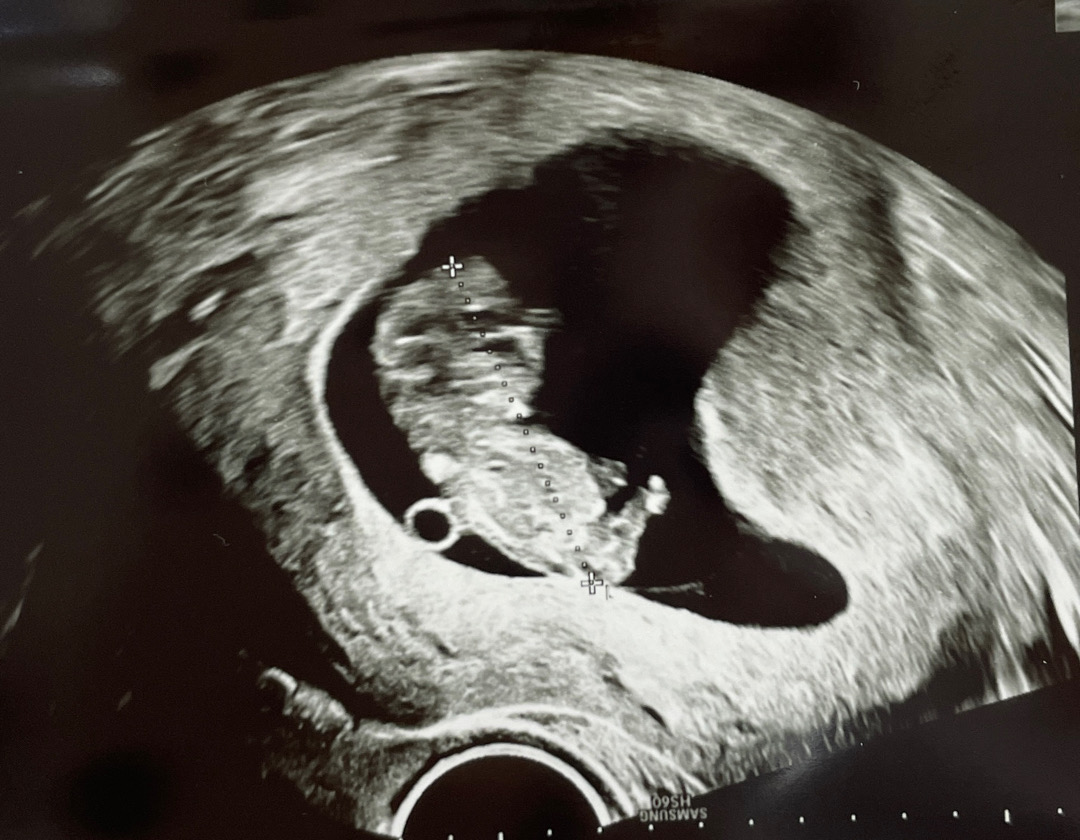

9주 6일차 병원다녀왔는데 촉에 딸같아요

9주 6일차에요 제법 사람 같아보였어요 발가락도 5개 갈라져있고 ㅎㅎㅎ 꼭 누워있는 폼이 딸같이 누워있네여 걍 제느낌이 ㅋㅋㅋㅋㅋㅋㅋ 딸같나요? 아들같나요? 저희신랑 제가 이거 올리고 성별 물어본 거 알면 진짜 비웃고 어이없어 할 것 같지만 ㅋㅋㅋㅋㅋㅋㅋ 성별 넘 궁금하네요 ㅠㅠ ㅋㅋㅋㅋㅋ